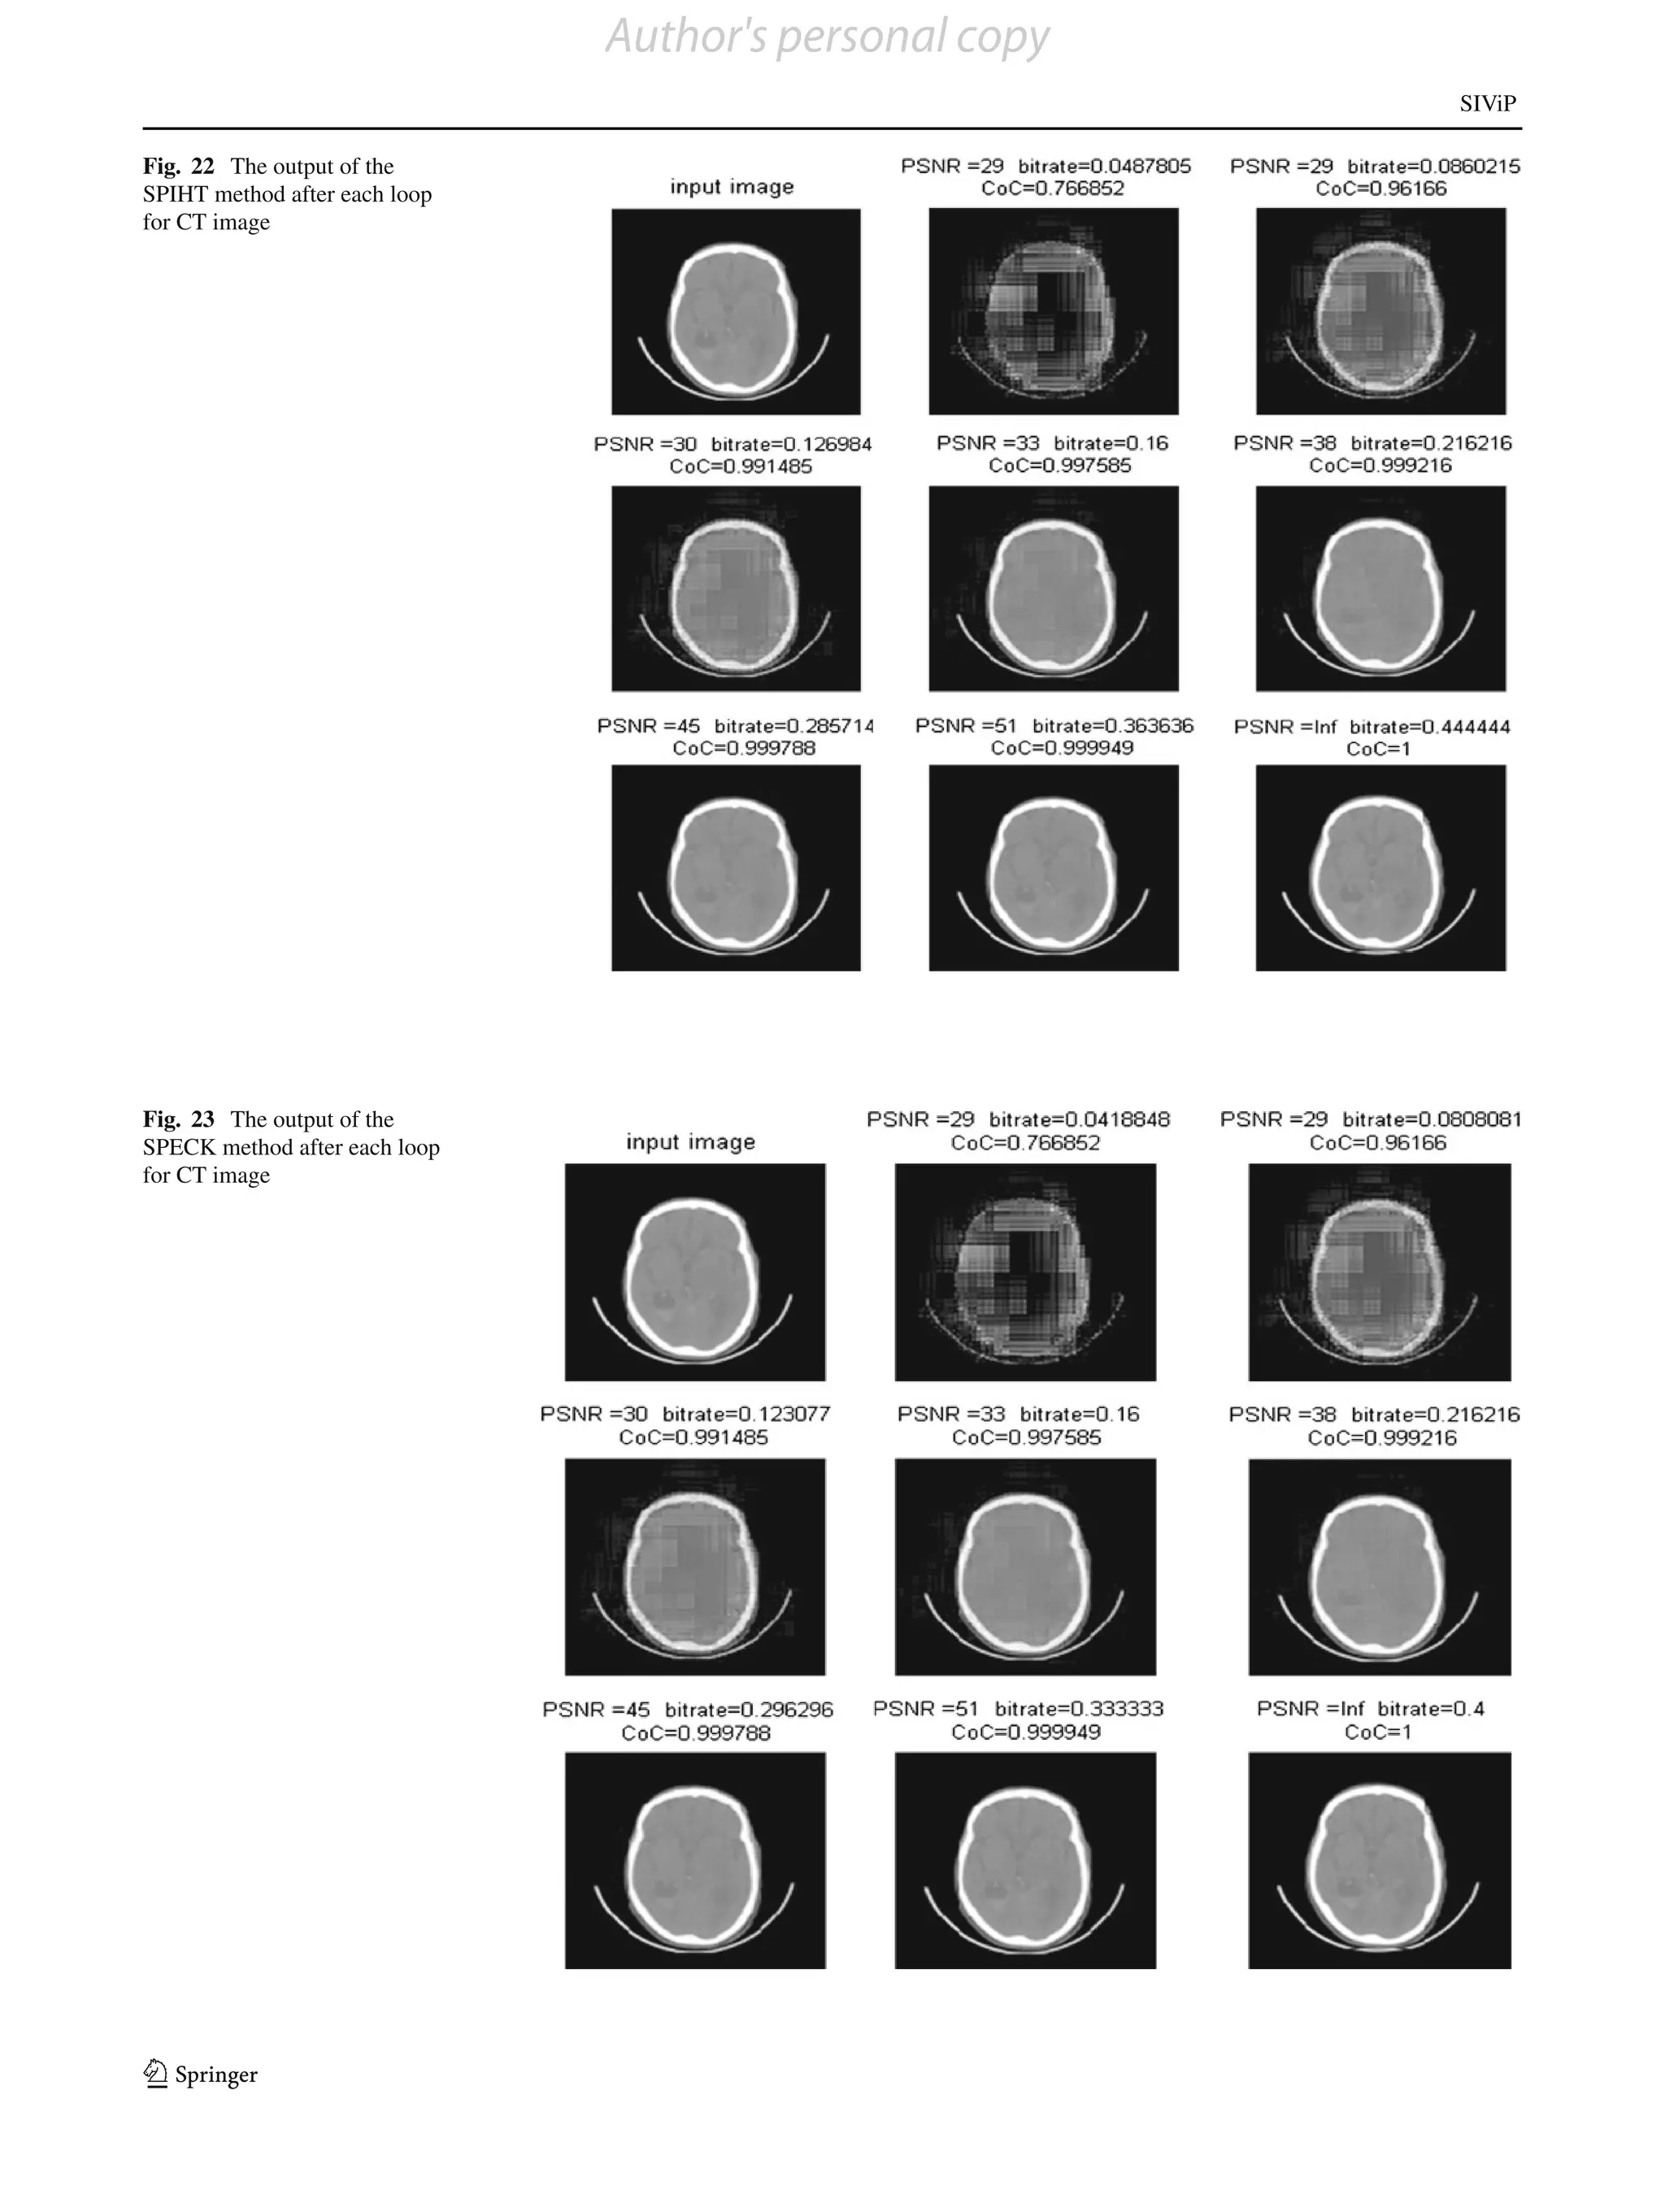

For CT images, all type of gray values exists. The outputs

after each loop for each method are shown in Figs. 21, 22, 23,

24 and 25. In each figure, the first image shows the input and

second image onward shows the output after each loop. The

comparative results of the bit-rate versus PSNR are shown

in Table 7, and the corresponding plots are shown in Fig. 26.

Fig. 22 The output of the

SPIHT method after each loop

for CT image

Fig. 23 The output of the

SPECK method after each loop